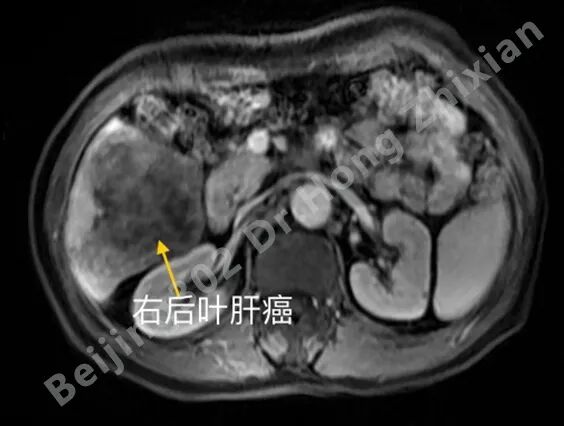

临床随笔丨肝癌术前新辅助治疗:“更优选择”还是“过度治疗”?

病例简介